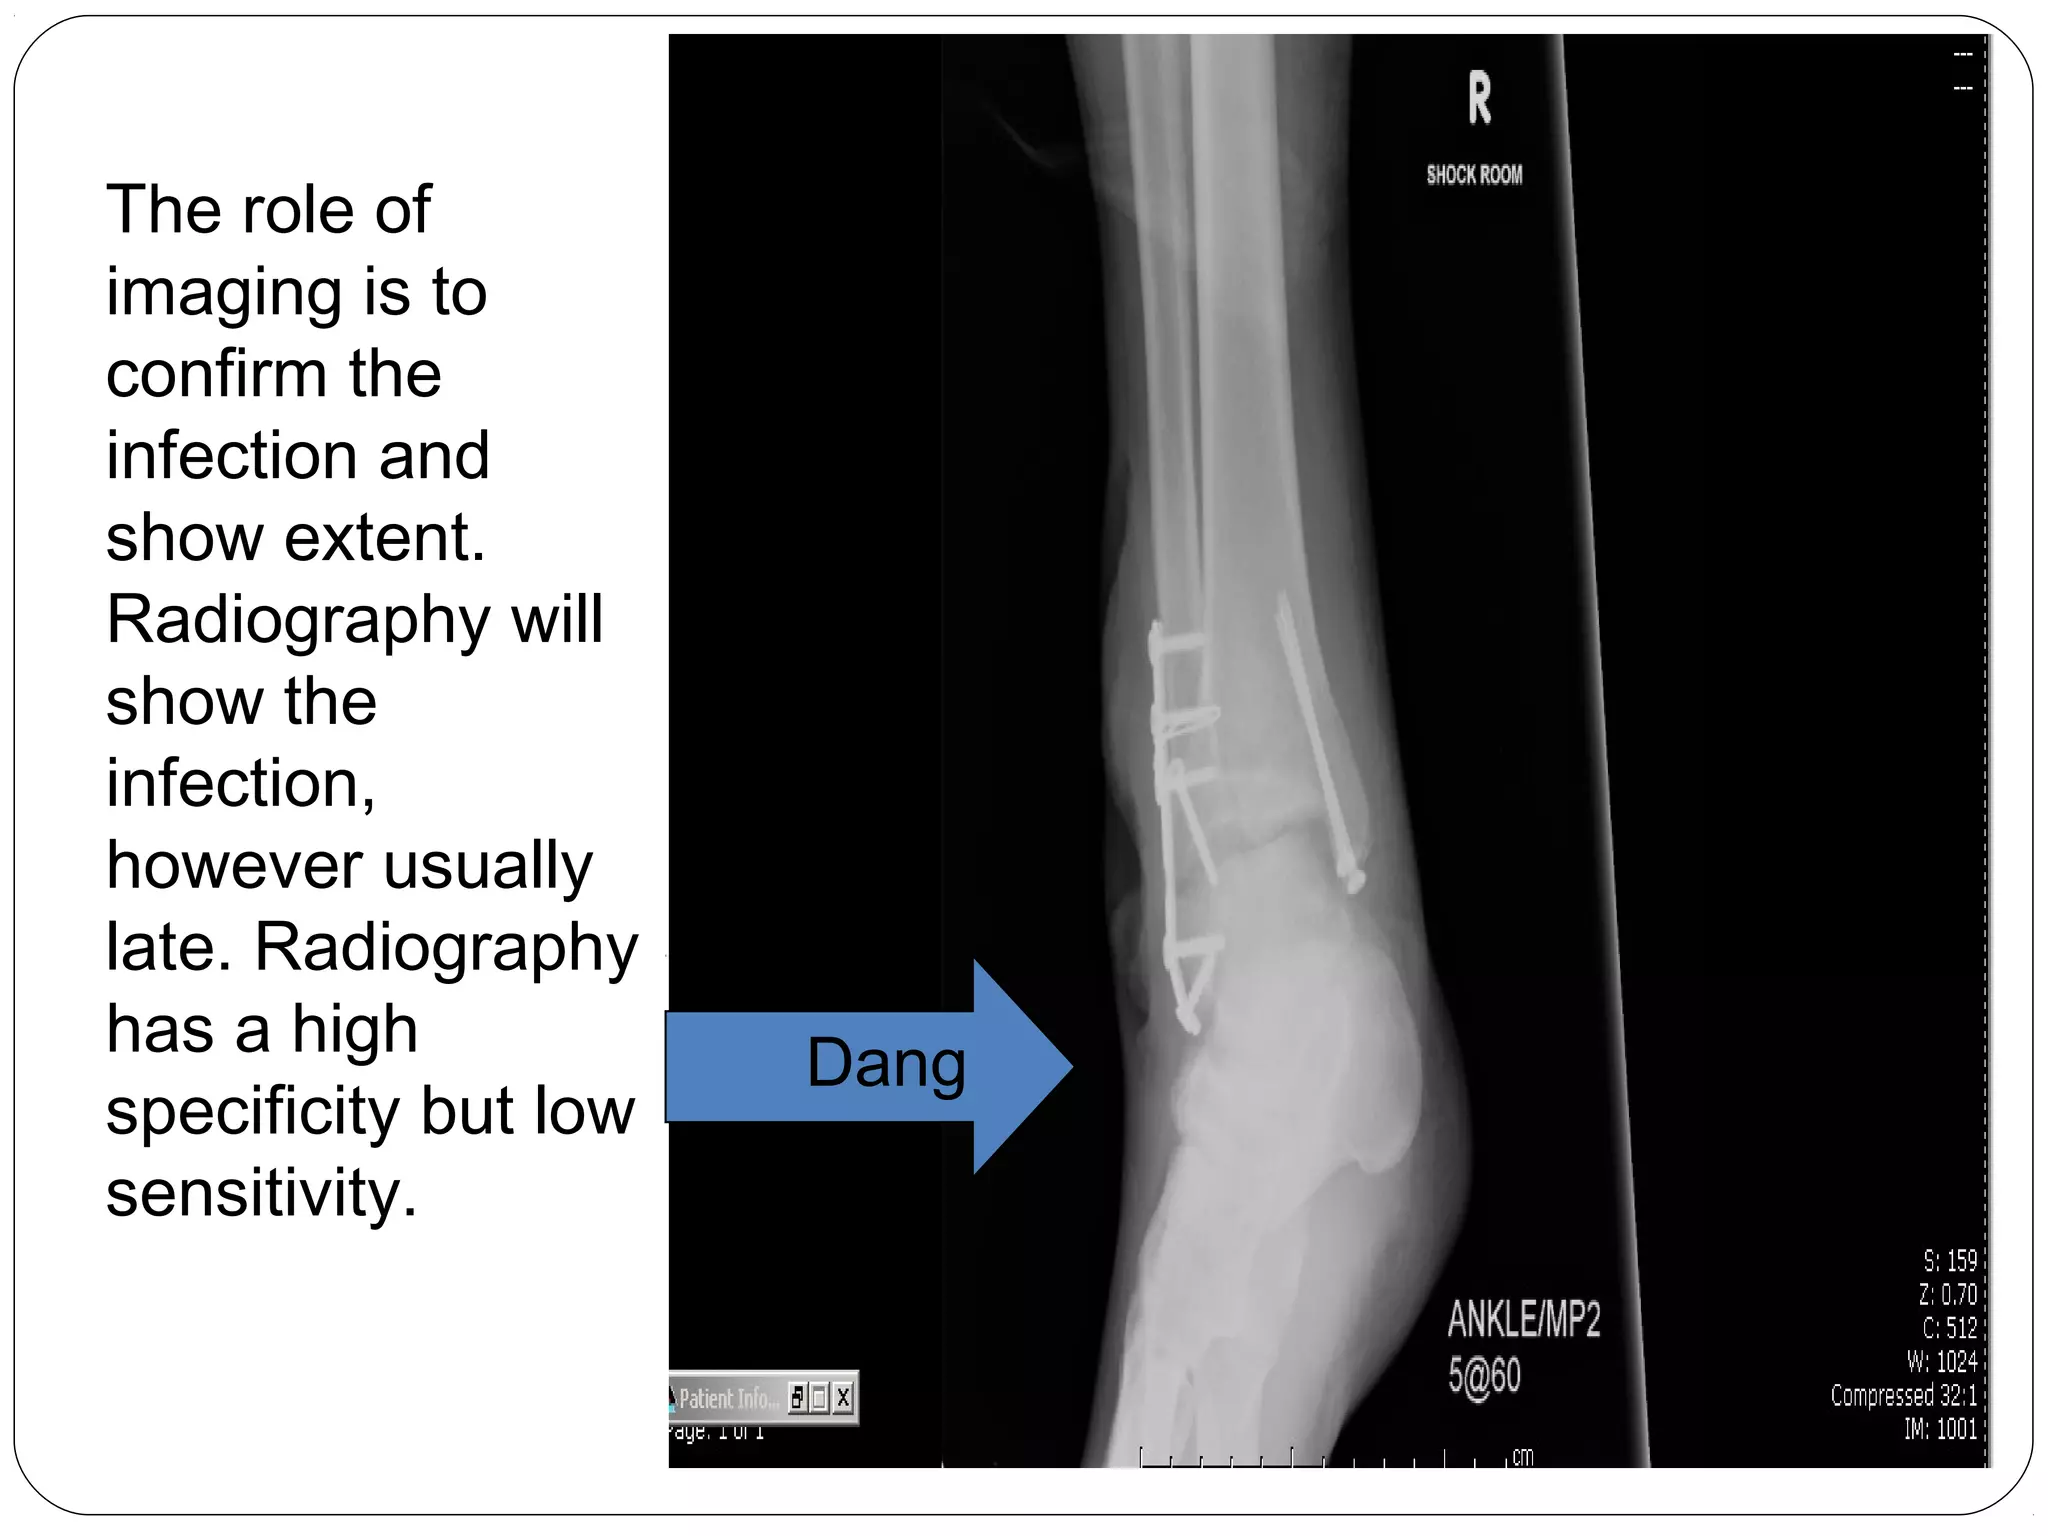

Dang

The role of

imaging is to

confirm the

infection and

show extent.

Radiography will

show the

infection,

however usually

late. Radiography

has a high

specificity but low

sensitivity.